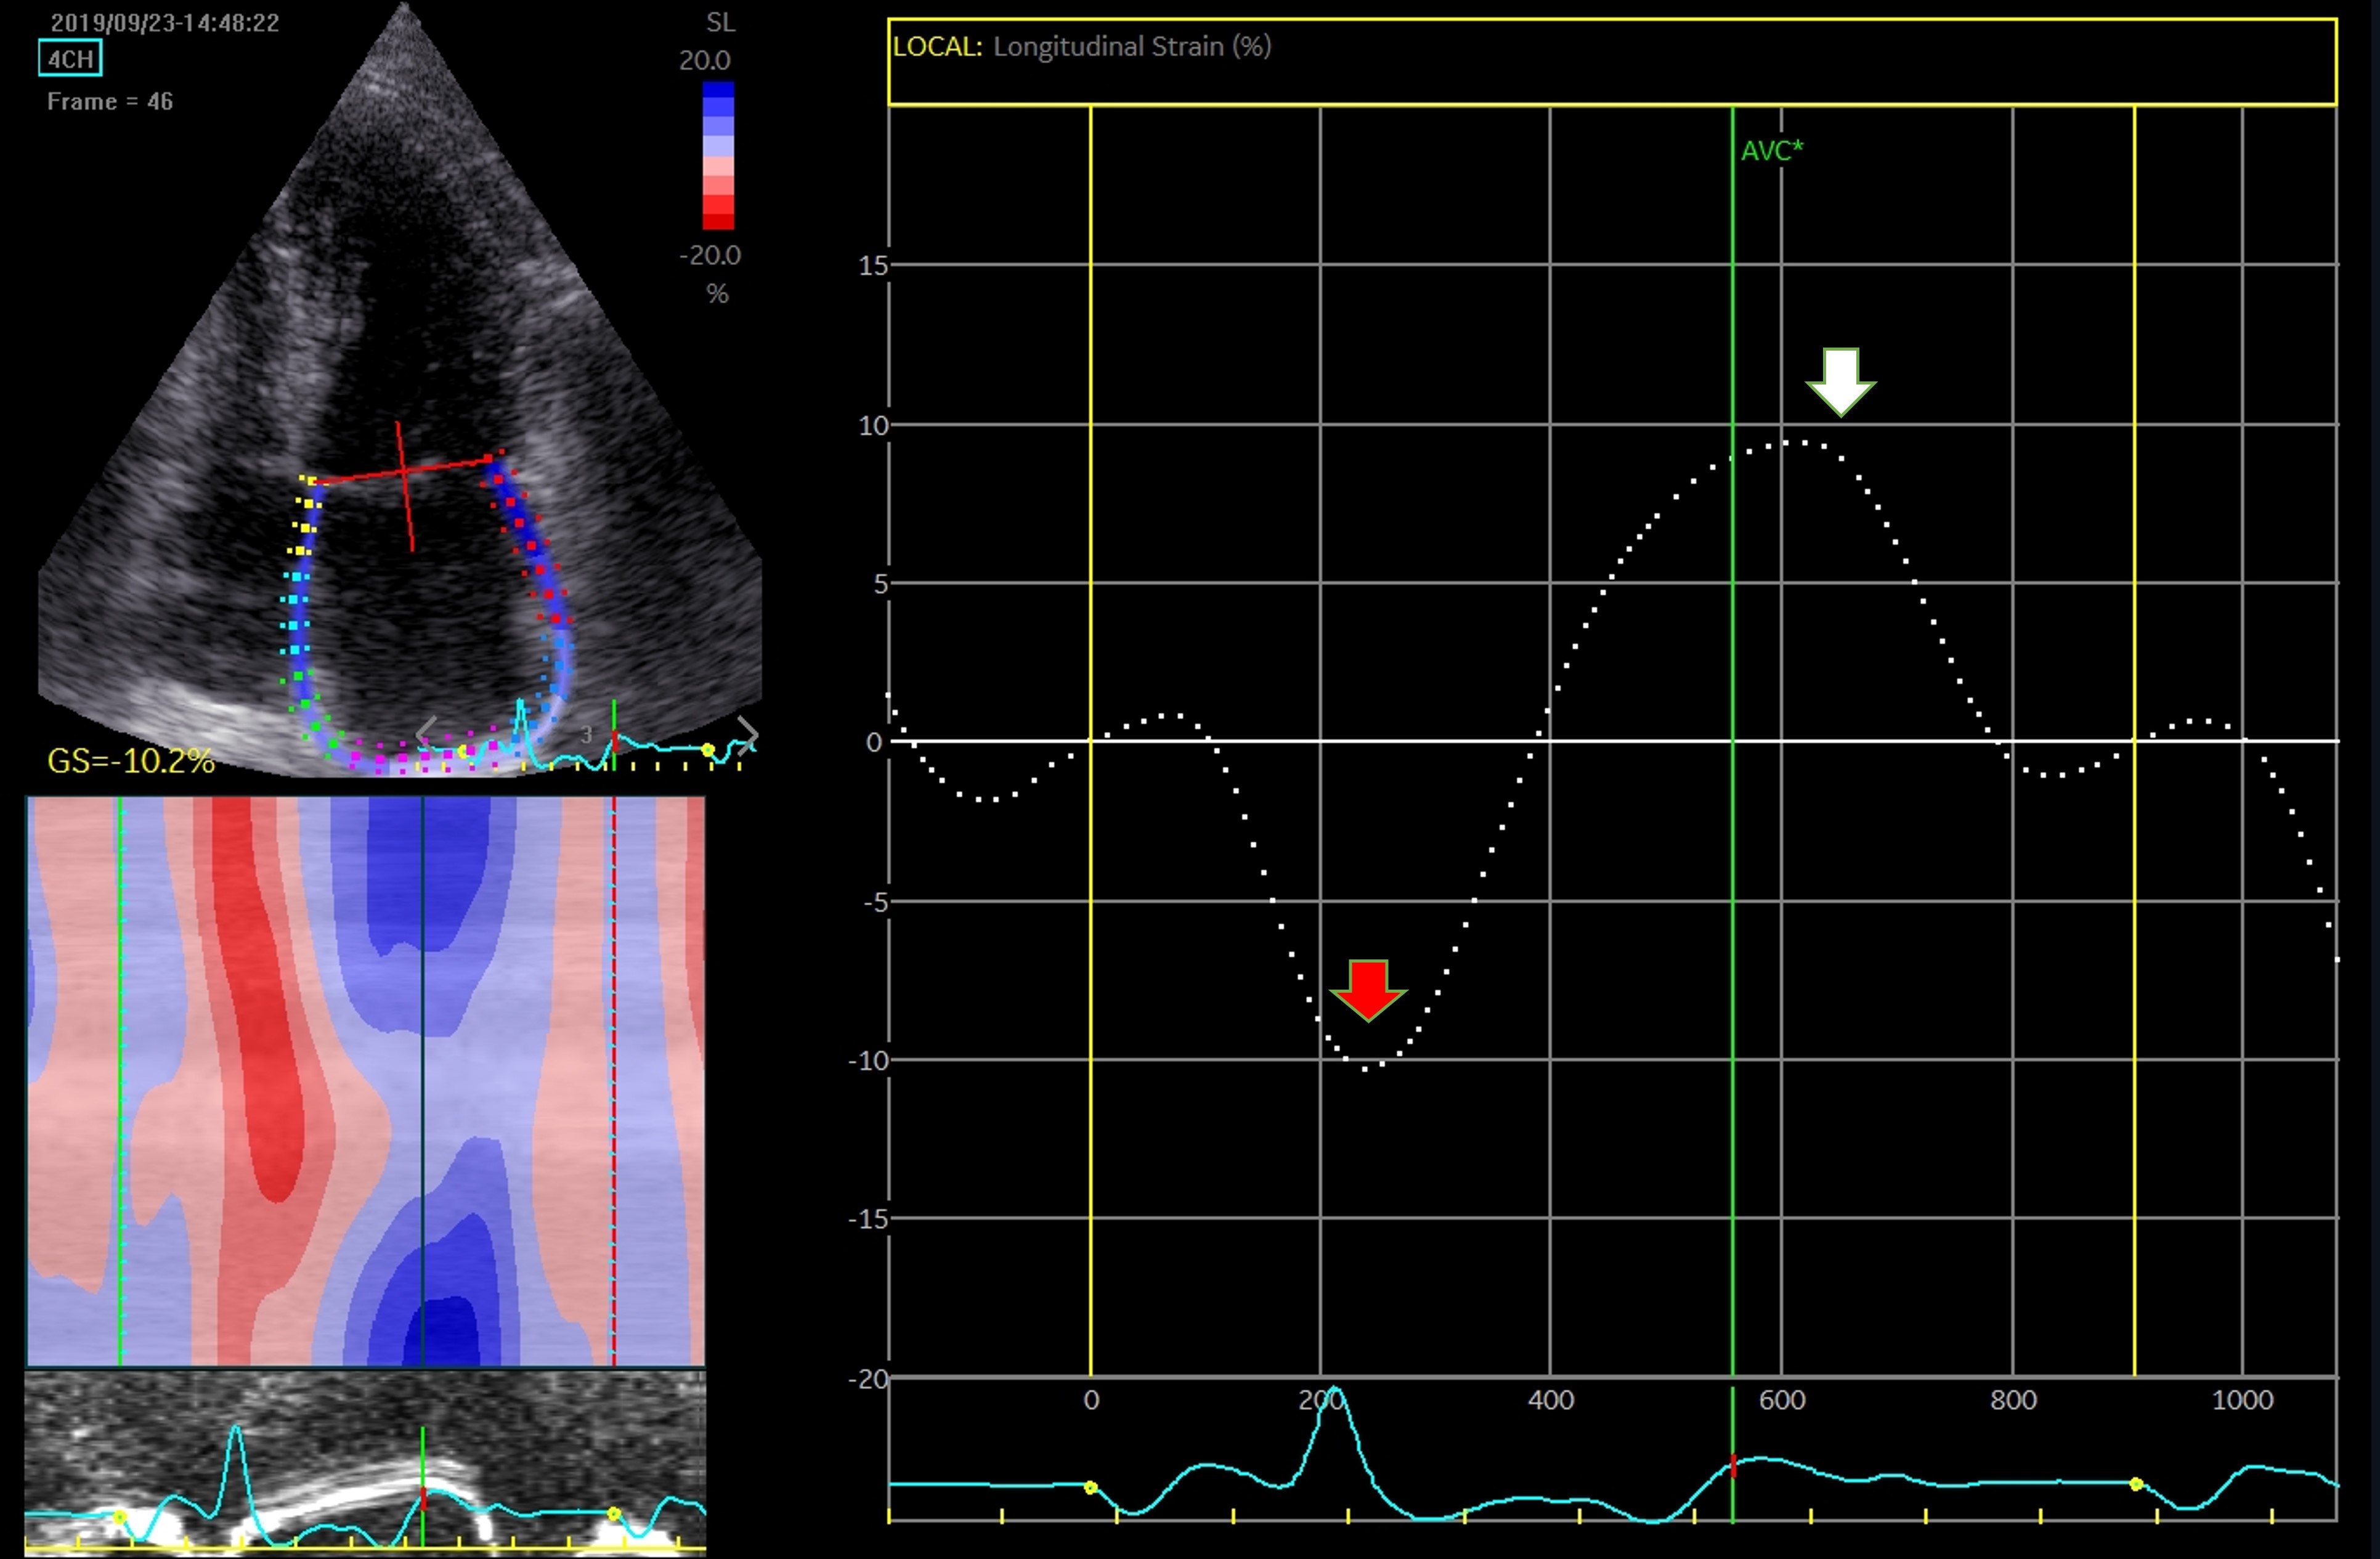

Strain analysis has the advantage of being a semi-automated, angle-independent technique. The need to manually track the LA walls and reposition the region of interest on each segment, makes this investigation time consuming and decreases reproducibility. Until recently, studies relied on a single software, and consensus and interchangeability between different software are still needed. Irrespective of these limitations, atrial strain is validated and correlates with the degree of fibrosis [88]. The assessment can address a 4-chamber view (6 segments) only, or both 4- and 2-chamber views (12 segments), in dedicated optimized views to record a maximized cross-sectional image of the chamber. The recommendations highlight exclusion of pulmonary veins and appendage orifice [53]. Interpretation of LA strain as global strain is advised, while using a single apical 4-chamber view to assess LA longitudinal strain is acceptable. Notably, the interatrial septum is more difficult to visualize. This is the reason why most studies disregarded the interatrial septal deformation and focused on lateral wall movement [89]. The LA septal strain is influenced by its fibromuscular composition and by right atrial pressure. In 2- chamber view, the problem of strain analysis depends on the LA appendage, which often compromises the recognition of speckles and deformation analysis [90]. The measurements may be interpreted using the QRS-complex [53] or the P-wave intervals [91], with similar reproducibility, but better feasibility and shorter time-to-analysis for the former (Figs. 8,9). Moreover, the QRS-complex interval has an advantage when assessing patients with arrhythmias, as AF [92].

Fig. 8.

Fig. 8.Assessment of LA function by speckle tracking echo using the R-R interval – peak systolic LA strain (arrow). Four-chamber view depicting the region of interest (ROI, in the left). The curves represent the mean global LA longitudinal strains. The reference point was set at the onset of the R-wave. The total global strain is positive at the opening of the mitral valve (red arrow). Global strain at atrial contraction is also positive (white arrow). The total global strain is a sum of the negative global strain at atrial contraction (red arrow – at mitral valve closure) and the positive global strain (white arrow – at mitral valve opening).

Fig. 9.

Fig. 9.Strain evaluation of the left atrium using the P-P interval. Four-chamber view depicting the region of interest (ROI, in the left). The curves represent the mean global LA longitudinal strains. The reference point was set at the onset of the P-wave. The total global strain is a sum of the negative global strain at atrial contraction (red arrow – at mitral valve closure) and the positive global strain (white arrow – at mitral valve opening).

The limitations of the method include the location of the LA, reduced signal to noise ratio, a thin wall, and the presence of pulmonary veins and LA appendage. These particularities make the LA strain analysis more difficult and time-consuming compared with left ventricle strain evaluation [90].

LA strain of the reservoir phase (LAS-r) corresponds to LA early diastole (peak atrial longitudinal strain - PALS); LA strain in the conduit phase (LAS-cd) corresponds to LA mid-diastolic emptying with its passive shortenings while LA strain in the contraction phase (LAS-ct) or peak atrial contraction strain (PACS) corresponds to LA systole with active myocardial shortening that produces the atrial contribution to ventricular filling. In normal individuals, the reservoir, passive conduit, and pumping phase account for 40%, 35%, and 25% of left ventricular filling, respectively [90]. There is no single measurement that can be used to determine LA function, and several parameters have been used in clinical studies. Nevertheless, the global function is best reflected by the reservoir strain [53, 54].

Strain measurements, LA reservoir, and conduit strain vary with age. They are significantly lower by the sixth decade, and between genders. During this time, the LA contractile strain improves, as a compensatory mechanism, and this mechanism is predominant in males [93].

Compared to SR patients, in patients with AF, the reservoir and conduit strain are decreased, while the atrial contraction is absent. The alteration of the reservoir function may be detected even before AF development, as a consequence of LA fibrosis and reduced compliance. Reservoir function by LA speckle tracking has an inverse linear relationship to cardiac magnetic resonance late gadolinium enhancement detecting fibrosis, thus evaluation of the function before a procedural approach may be a strong predictor of outcome [47]. After SR restoration, reverse atrial remodeling is reflected by an increase in LA reservoir function and passive conduit strain [94]. This improvement in the LA reservoir function may be approached as a marker of a successful outcome and could show its value in the early recognition of patients with AF recurrences [95].

A reduced LA active pump function independently predicts new-onset AF [96],

while the LA strain is strongly associated with AF recurrences after ablation

[97, 98] and may even predict evolution toward non-paroxysmal episodes [37].